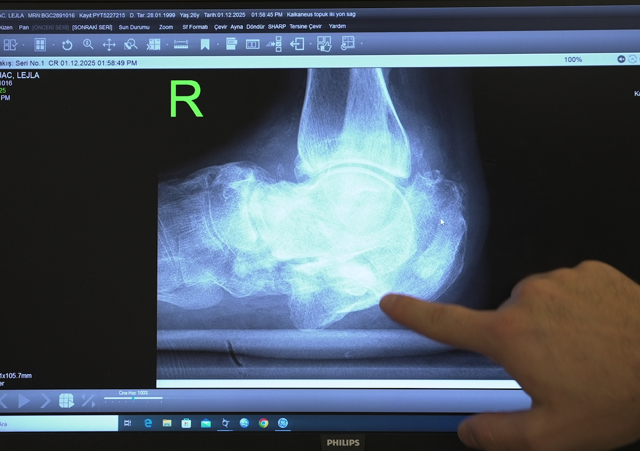

Diyabetle gelen sağlık sorunlarına değinen Doç. Dr. Çatal, “Hastamız 26 yaşında ve uzun yıllardır kontrolsüz diyabeti bulunuyor. Diyabet hastalarında ayaklarda his kaybı oluşabiliyor. Bu nedenle küçük bir kırık bile fark edilmeden ilerleyerek ciddi deformasyonlara yol açabiliyor. Hastamızda topuk kemiğinde, yani kalkaneus dediğimiz kemikte ciddi bir kırık gelişmiş. Üzerine basmaya devam ettikçe ayağında genişleme oluşmuş. Ameliyatta topuk kemiğini yeniden yapılandırdık. Kalça kemiğinden aldığımız kemik greftleriyle bir ‘kurtarma cerrahisi’ uyguladık. Amacımız, hastanın ağrısız ve düzgün basabileceği, normale en yakın anatomiyi sağlamaktı. Bu hedefe ulaştık.” diye konuştu.

Sırbistan’da “ayağın kesilecek” dediler, Türkiye’de yeniden yürüdü! Medipol’de uygulanan tedavi sayesinde... - Resim: 0